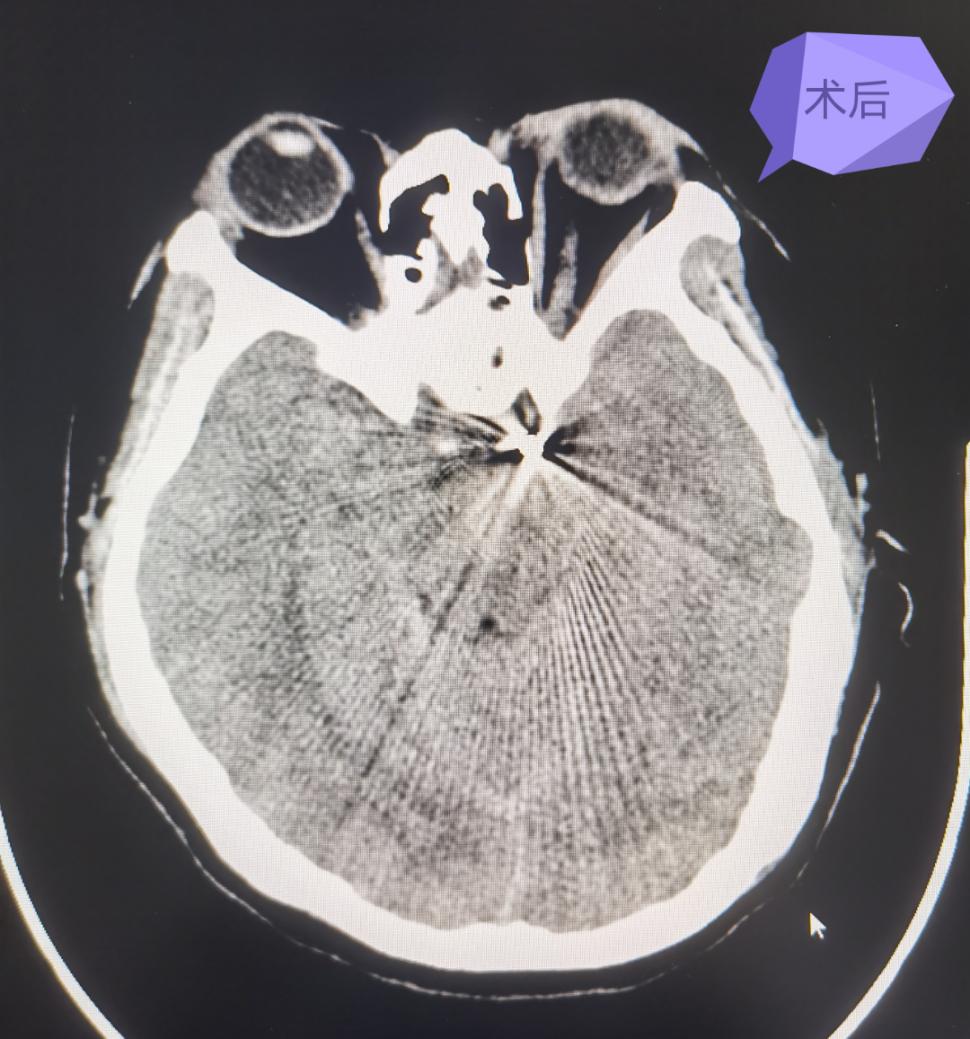

术后

手术顺利,术后第3天患者意识清楚,对答正确,右侧肢体肌力4级,术后第5天患者已下地活动。